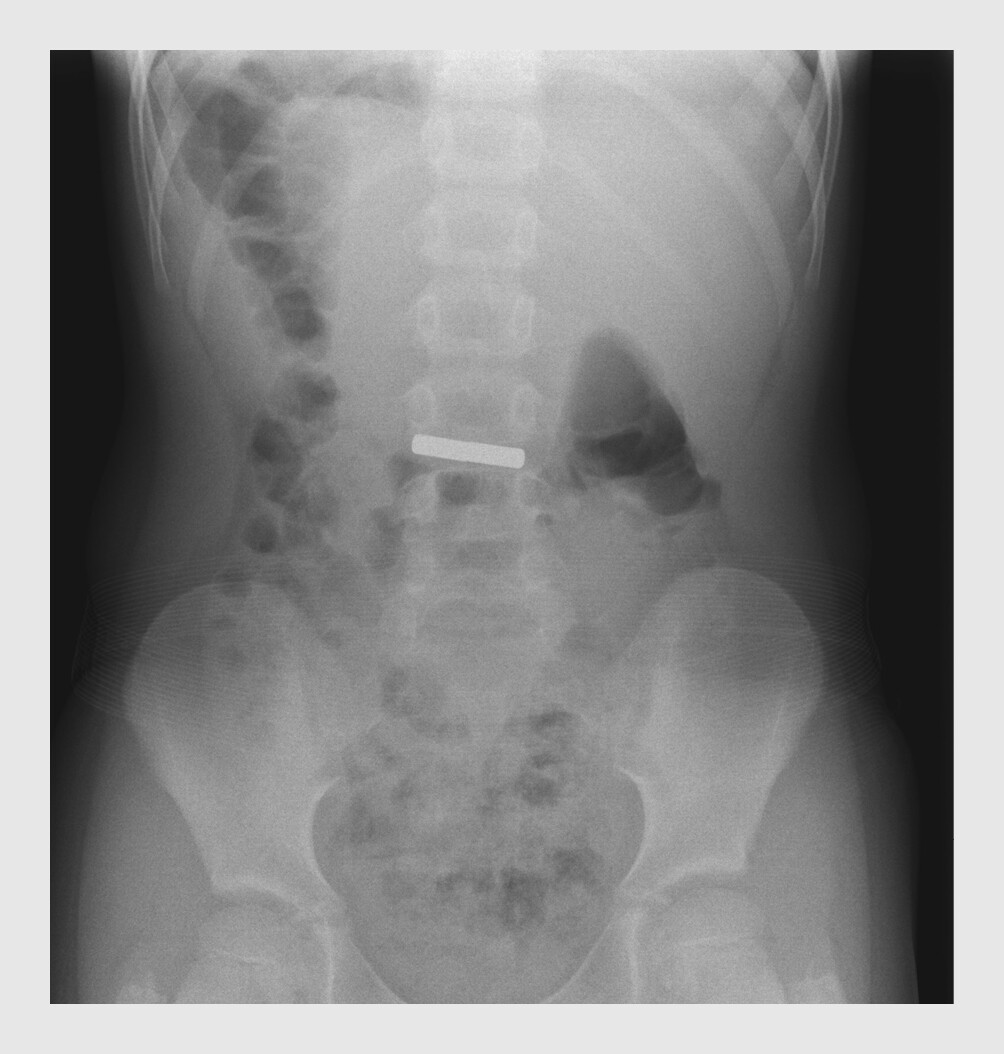

Patiënt B, een 6-jarig meisje met een blanco voorgeschiedenis, kwam direct met haar ouders naar de SEH, nadat zij 2 aan elkaar vastzittende, staafvormige koelkastmagneten had ingeslikt. Uit de anamnese en het lichamelijk onderzoek kwamen geen relevante bijzonderheden naar voren, met name geen respiratoire symptomen, maag-darmproblemen, kwijlen of koorts. De buikoverzichtsfoto toonde een radio-opaak, staafvormig voorwerp dat zich voorbij de maag bevond (figuur 1). Omdat het voorwerp ver voorbij de maag gelokaliseerd was, was het technisch gezien niet mogelijk om het voorwerp endoscopisch te verwijderen. Er was geen indicatie voor een chirurgische ingreep, aangezien patiënte geen klachten ervoer. Patiënte werd behandeld met macrogol 40 g/dag (2 g/kg). Ook kreeg instructies om terug te komen naar de SEH wanneer zij klachten kreeg, zoals buikpijn of melena. Binnen 48 uur werden beide magneten teruggevonden in de ontlasting. Het verdere beloop was ongecompliceerd.

Figuur 1

Ingeslikte koelkastmagneten

Figuur 1 | Ingeslikte koelkastmagneten

Buikoverzichtsfoto van patiënt B waarop voorbij de maag een radio-opaak, staafvormig voorwerp – 2 aan elkaar vastzittende koelkastmagneten – te zien is. Het is op basis van de foto niet duidelijk of het voorwerp zich in de dunne of dikke darm bevindt.